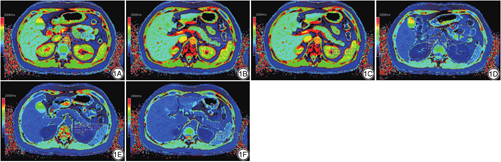

T1 mapping图像扫描后传输至西门子Syngo Via后处理工作站,生成伪彩图。利用椭圆测量工具绘制感兴趣区(region of interest,ROI)。通过参考常规T1W1及T2WI轴位图像,避开主胰管、胰腺周围的血管、脂肪、坏死成分等结构,将相同大小的ROI (大小控制在50 mm2左右)放置在信号均匀的胰腺实质内。在增强前及增强后的T1 mapping图像中,ROI分别放置于胰头、胰体、胰尾部(图1)及同层面的主动脉内测量T1弛豫时间值,获取增强前后胰腺头体尾部三处的平均测量值作为胰腺实质的测量值,记为T1pre pancreas、T1post pancreas;获取增强前后主动脉内的平均测量值记为T1pre blood及T1post blood。增强前及增强后ROI放置的位置保持一致。所有的测量工作由2名具有3年以上诊断经验的放射学医师在未知临床资料的条件下独立测量,当2名医师测量结果的一致性较高时[组内相关系数(intraclass correlation coefficient,ICC)值>0.75],取二者测量结果的平均值作为最终结果;若二者测量结果一致性较差(ICC值<0.75),则由另一名高年资医师(具有23年诊断经验)进行测量作为最终结果。

2名放射科医师评价之间的一致性较高,ICC值为0.92。如表2所示,SAP组与RAP组间的平均T1pre pancreas、T1post pancreas及PER参数的差异均不具有统计学意义。RAP组的ECV值(0.41±0.10)高于SAP组(0.35±0.20) (图2),且其差异具有统计学意义。当ECV值大于0.38时,诊断RAP的准确度为0.72 (图3)。与正常组相比,AP组的T1pre pancreas、T1post pancreas、PER及ECV值均明显升高(P<0.05) (图4)。当利用T1pre pancreas>915.8 ms、PER>0.518及ECV>0.327指标分别独立诊断AP时,其受试者工作特征(receiver operating characteristic,ROC)曲线下面积分别为0.96、0.94及0.89 (表3)。